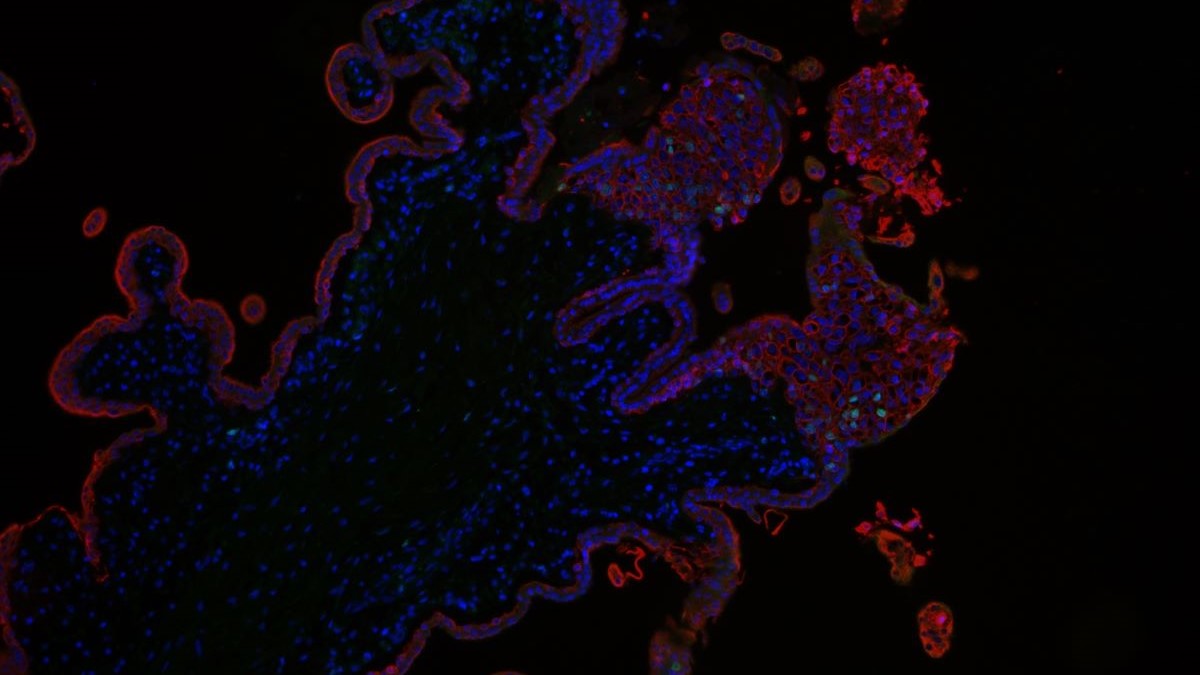

PFAS können Plazentaentwicklung stören